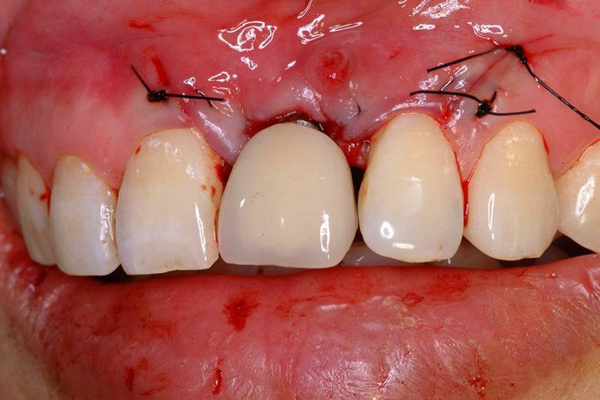

牙周炎圖片

牙周袋 (7)

牙周袋 (8)

牙周袋 (9)